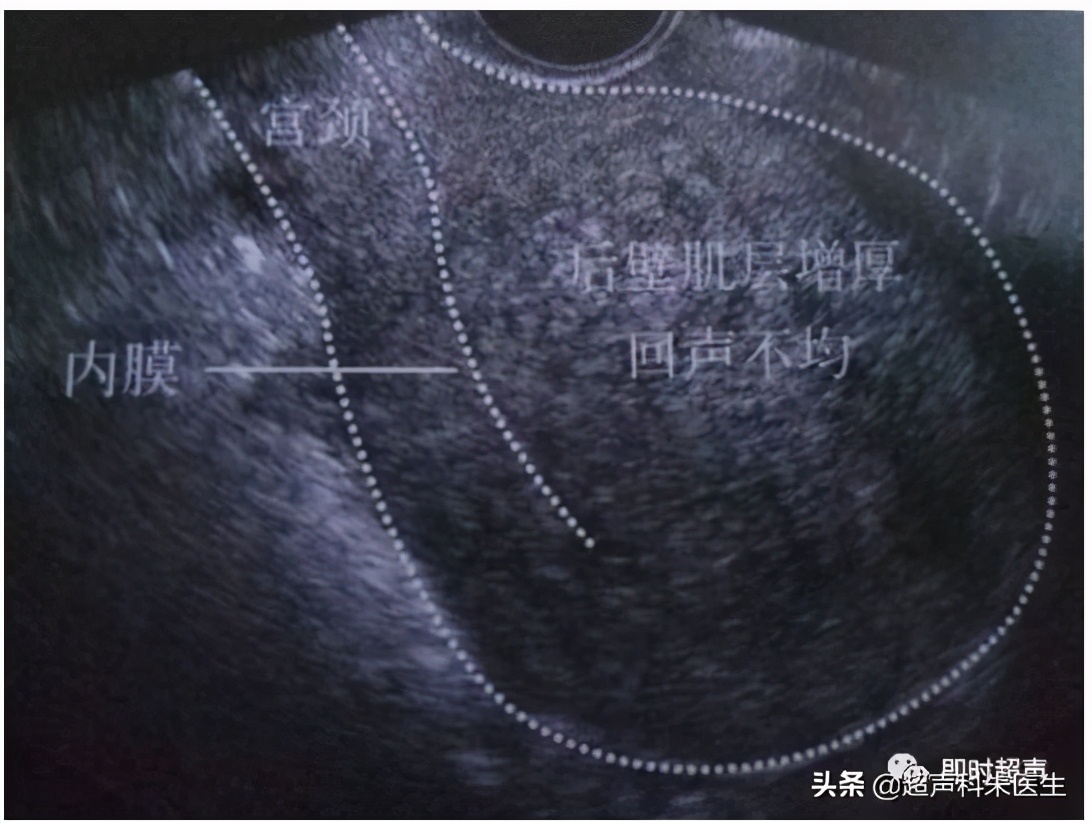

②子宫宫腺肌瘤、腺肌症

●子宫腺肌瘤时子宫呈均匀性增大

●肌层增厚,内可见多个小的无回声区(由囊状积血所致)

●子宫大小和内部回声,月经前后比较常有变化

●形成腺肌瘤者,可使子宫呈局限性隆起,呈非对称性增大,肿块边缘不规则,边界不清晰,无包膜回声,以子宫后壁居多。

子宫腺肌症